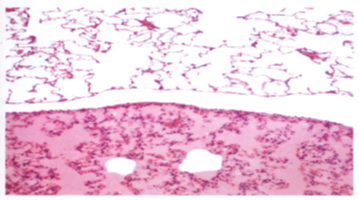

What is happening here?

Pulmonary edema with widened interlobular septa

What organ is this, which one is normal, and what is happening in the abnormal one?

Lung; top is normal; bottom has pulmonary edema - protein-rich fluid filling alveoli and congested alveolar septa